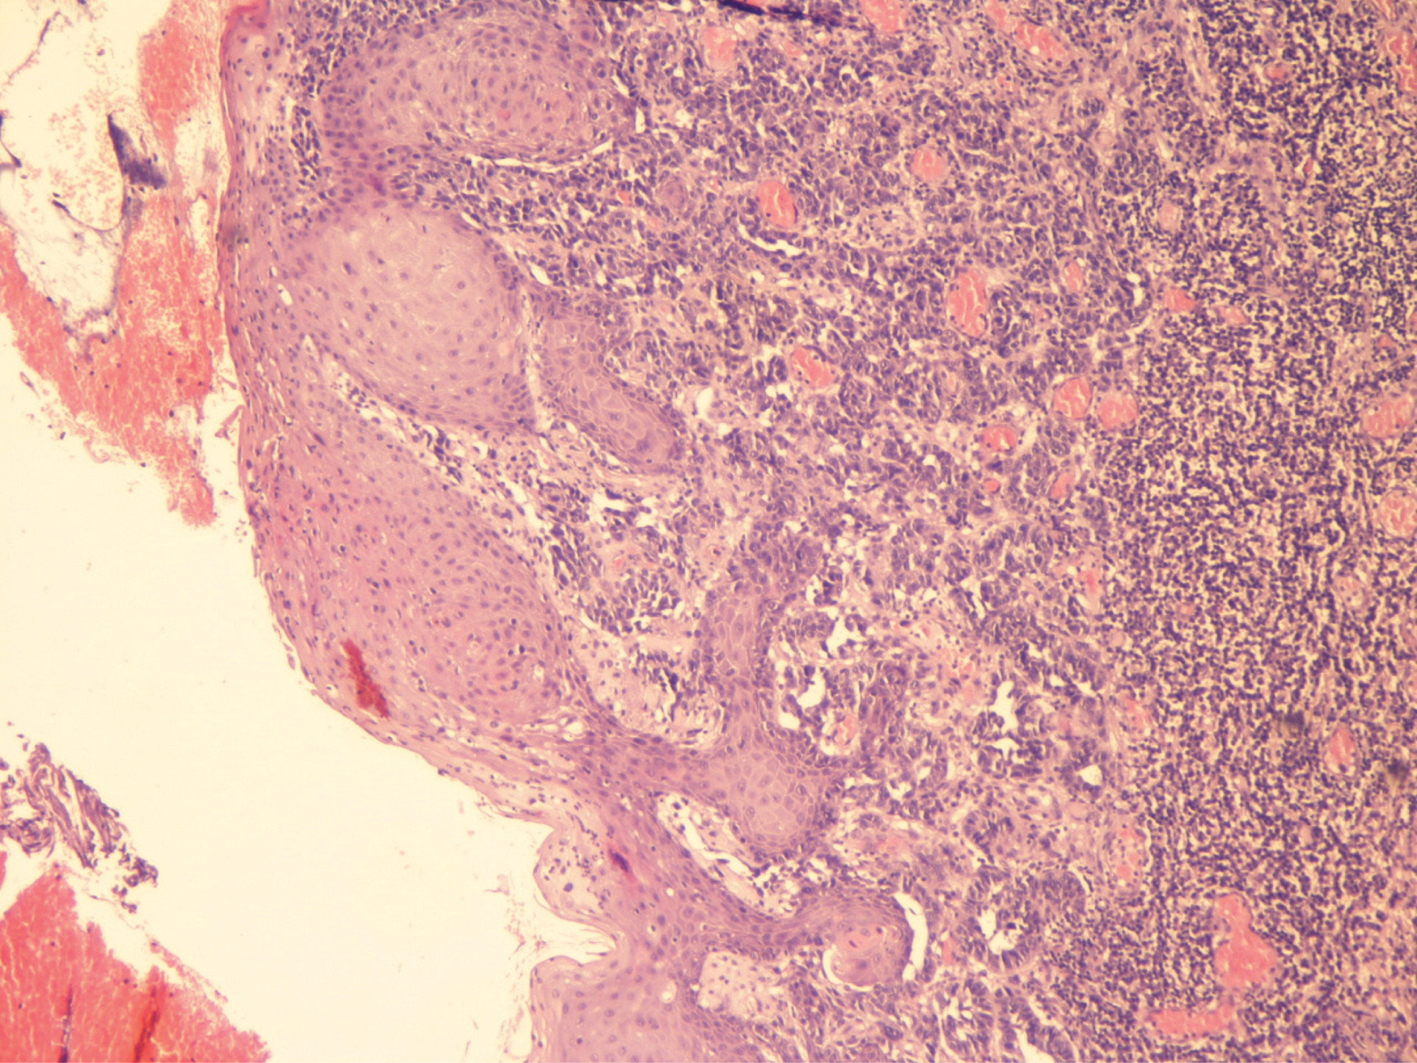

NPM is often amelanotic, resembling a benign polypoid lesion. Therefore, histology plays a pivotal role for a correct diagnosis (Figures 1 and 2). However, NPM can be also confused with other tumors, such as undifferentiated small blue cell tumors of the sinonasal tract, including olfactory neuroblastoma, sinonasal undifferentiated neuroendocrine carcinoma, Ewing’s sarcoma, peripheral neuroectodermal tumor (PNET), and rhabdomyosarcoma. Other differential diagnoses include squamous cell carcinoma and non-Hodgkin lymphoma. Accordingly, immunohistochemistry also plays an important role in the diagnosis. Human melanoma black (HMB)-45 reaches the 100% specificity for melanoma, while Melan-A is slightly less specific (2930). According to Morris et al., PNL-2 is a highly sensitive marker for mucosal melanoma, superior to Melan-A and microphthalmia-associated transcription factor (MITF) and comparable with HMB-45 (29). Therefore, PNL-2 can be evaluated as an important adjunctive marker in the immunohistochemical evaluation of PMMs (26, 27). Furthermore, it is often difficult to distinguish a metastasis from a primary neoplasm. However, a de novo primary NPM is much more likely than a metastasis, although at the time of diagnosis, up to 50% of patients with primary NPM develop distant metastases to the brain, liver, and lungs (3). Therefore, after a diagnosis of an NPM, it is important to perform a general dermatological consultation, followed by a trachea-laryngoscopy, gastro-duodenoscopy, colonoscopy, and ophthalmological consultation, in order to exclude other localizations.

Fig 1

Figure 1 A rare histological image of a dermal, pleomorphic malignant melanocytic proliferation of the oral cavity, in a nonkeratinized epithelium. (Hematoxylin and Eosin, 20×) Courtesy of Dr. Angelina Pernazza.